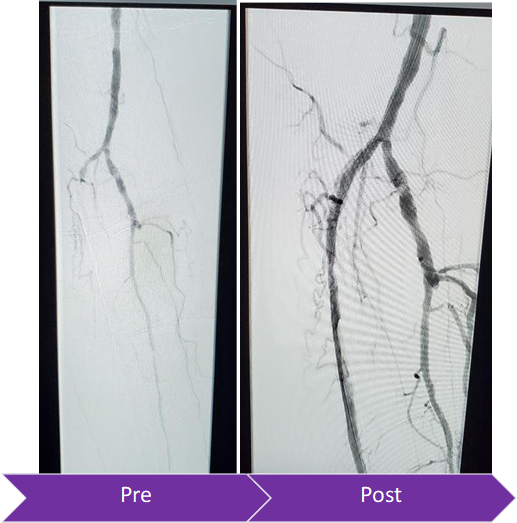

Congratulations and thank you to @RicardoBCardiel, @surgmax, and the entire team at Presbyterian Hospital for a successful FIRST Peripheral #ROTAPRO Case! #CLTI

bsc_vascular's tweet image. Congratulations and thank you to @RicardoBCardiel, @surgmax, and the entire team at Presbyterian Hospital for a successful FIRST Peripheral #ROTAPRO Case! #CLTI